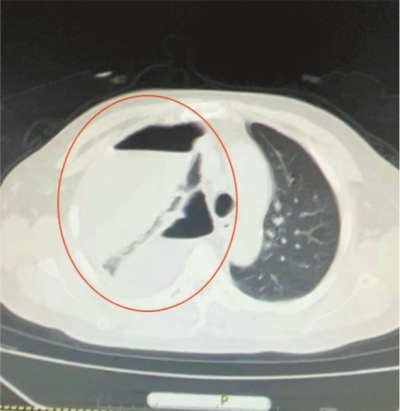

12月18日,53岁的何先生因肚子不舒服、排便不畅到家附近的武汉科技大学附属普仁医院就诊。起初,他以为就是普通的肠胃问题。接诊后医生发现,何先生行走不稳,还伴有胸闷气短的症状,血氧饱和度连90%都不到,呈现出明显的急性病容。反复追问得知,何先生10天前不慎摔倒,磕到了胸部,当时没有进行处理。这一细节引起了医生的警觉,他们立即为他安排了胸腹部CT检查。结果一出,在场所有人都震惊了:右侧胸腔里存在大量液气胸,整个右肺已经完全被挤瘪,情况十分危急。心胸外科团队迅速行动,在急诊床旁为何先生实施了胸腔闭式引流术,引流出大量气泡和散发浓烈臭鸡蛋味的咖啡色脓液。数量之多、颜色之深、味道之浓,在场的医护人员均表示“头一回见”。3天的引流,何先生共排出了3000毫升脓液,胸闷症状得到明显缓解。

12月19日的检查结果发现,何先生的血生化和胸腔积液肿瘤指标有异常增高,医生们高度怀疑存在恶性病变的可能。心胸外科团队排除了手术禁忌证后,12月23日再次为何先生实施了胸腔镜下脓胸清除术。术中,可以清楚地看到在他的肺部和胸膜上布满了密密麻麻的脓胎,如同定时炸弹一样随时威胁着他的生命。医生精心操作,一一将这些脓胎清除干净,并切除了肺脓肿组织。经过抗感染、化痰、缓解气道痉挛等对症治疗,何先生的身体状况逐渐好转,不日即可出院。心胸外科主任王杰提醒市民,身体出现任何不适都不能掉以轻心,尤其是胸闷和腹痛等症状,可能隐藏着更为严重的健康问题。